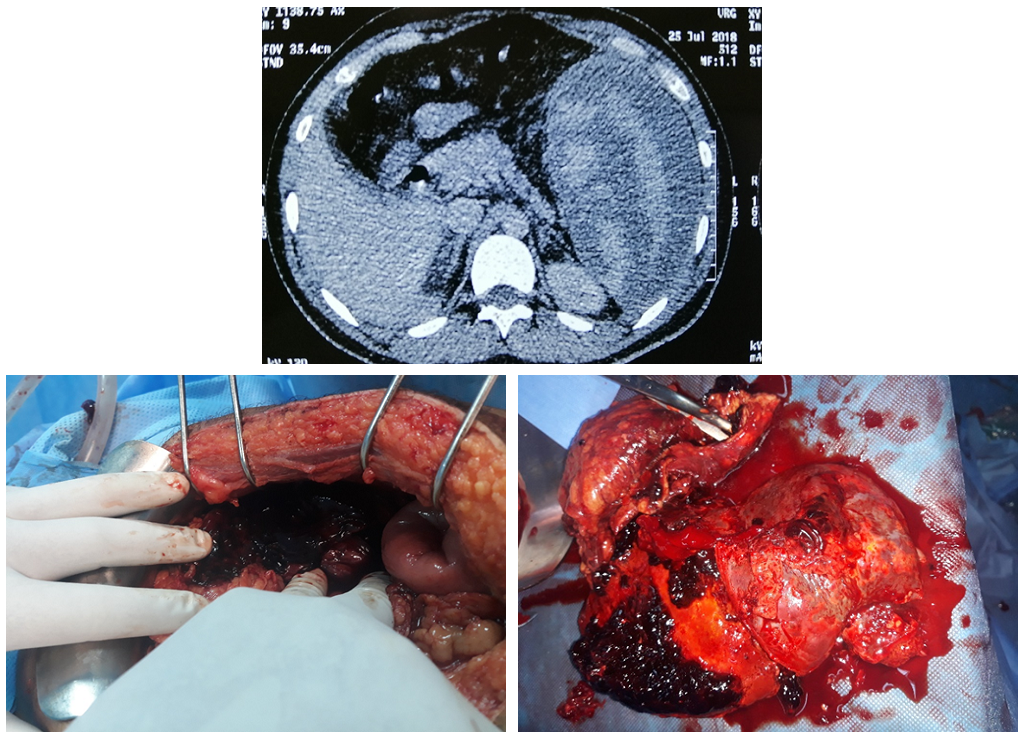

Open AccessCase Report

A Case of Spontaneous Rupture of the Spleen

Yasser El Brahmi, Mohammed El Fahssi, Anajjar Mohamed, Prosper Nsengiyumva, Ehirchiou Abdelkader, Abdelmounaim Ait Ali

International Journal of Innovative Research in Medical Science·June 25, 2020